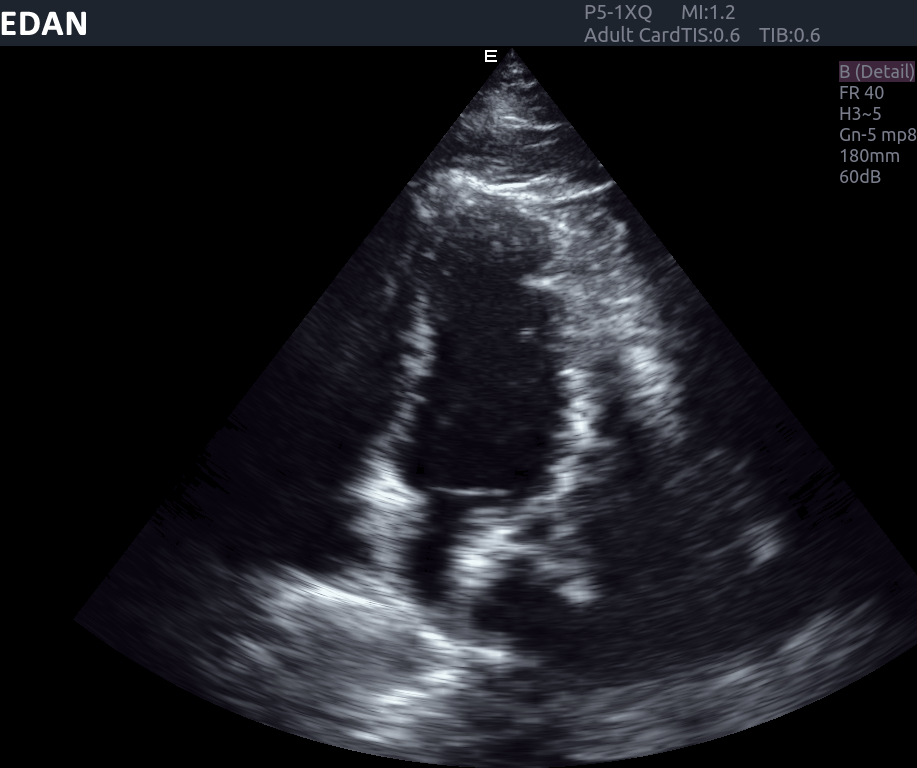

imagem do ultrassom edan ax8

Como soluções de ultrassonografia podem aprimorar diagnósticos, monitoramentos e procedimentos com precisão e mobilidade.

No contexto da insuficiência cardíaca, por exemplo, um dos modelos de ultrassons da linha AX da Edan, o AX8, permite avaliar a função ventricular global e segmentar, estimar pressões de enchimento e monitorar a resposta a terapias farmacológicas e dispositivos como o ressincronizador cardíaco.

O Edan AX8 é um sistema de ultrassom que reúne tecnologia de ponta para fornecer imagens de alta definição e recursos avançados de Doppler, aplicáveis a uma ampla gama de exames cardiológicos, como:

Além disso, a ecocardiografia desempenha papel vital na investigação de miocardiopatias, doenças congênitas e no acompanhamento de próteses valvares. A qualidade de imagem do AX8 contribui para diagnósticos mais rápidos e seguros, apoiando decisões clínicas em tempo real.

O Edan AX8 representa um avanço significativo para a cardiologia, unindo alta qualidade de imagem, recursos avançados de Doppler, tecnologia de visualização de agulhas e mobilidade. Essas características impactam diretamente a prática clínica, proporcionando diagnósticos mais seguros, monitoramento preciso e procedimentos guiados com maior confiabilidade.